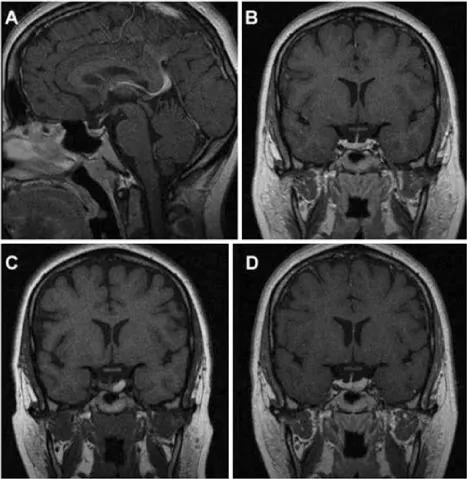

一项重要研究报道,在42例无症状垂体大腺瘤患者为期5年的随访中,近10%发生垂体卒中。这一风险在对意外发现的大肿瘤患者进行咨询时需特别强调。值得注意的是,微腺瘤同样可能发生卒中(图1),其实际发生率可能高于现有认知,但具体数据未知。Couldwell教授在随访意外发现的微腺瘤时,也会告知患者存在这一低概率风险。

图1,一名27岁女性患者的磁共振成像(MRI)资料,该患者因垂体微腺瘤接受William T.Couldwell教授的随访监测,后续发生垂体卒中。

A、B:初次就诊时获得的矢状位与冠状位T1加权增强MRI,显示垂体左侧部一小腺瘤。

C、D:随后复查的冠状位T1加权平扫及增强MRI,可见原肿瘤区域出现出血信号,提示腺瘤内卒中。